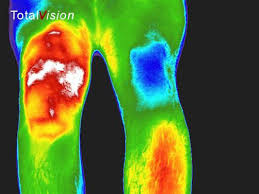

Vasculaire doorbloeding, spieren bij mens en dier en nachtzicht toepassingen.